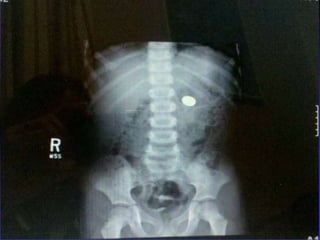

Foreign Body Airway Obstruction

FBAO

FBAO: High Risk Groups

 > 90% of deaths: children < 5 years old

 65% of deaths: infants

KIDS EAT EVERYTHING